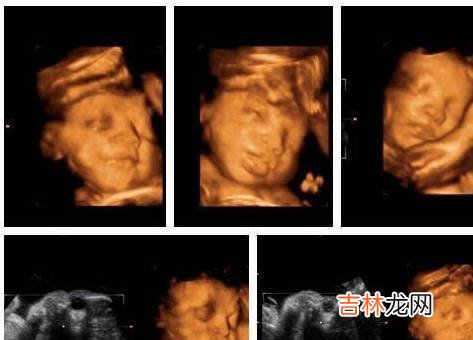

大排畸检查:大排畸检查的时间是孕20-28周 , 最佳时间是孕22-26周 , 主要是用来排查胎儿畸形的检查 , 确认胎儿宫内发育是否符合孕周 , 胎儿是否健康 , 四肢、头脑、内脏发育是否畸形 , 羊水以及脐带、胎盘的情况 。 大排畸检查包括三维彩超、四维彩超 , 检查需要提前预约 , 时间上不要太晚 。 大排畸检查虽然没有危险性 , 但是并不是万能的 , 还有很多畸形是检查不出来的 , 同时受胎儿的位置影响很大 , 如果胎儿不配合 , 位置不对 , 都会影响检查结果 。